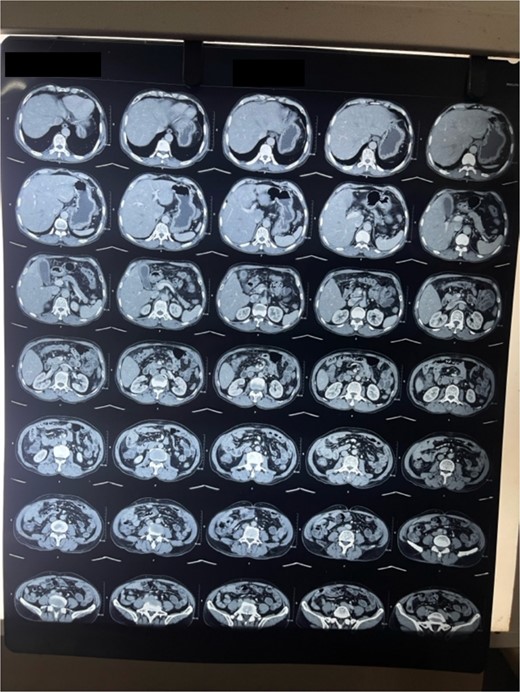

A 69-year-old male belonging to hilly region of Nepal was referred to BPKMCH with a suspected GB carcinoma for which triphasic computed tomographic scan of thorax abdomen and pelvis was done, which had revealed GB fundus mass with surrounding liver lesion. Ultrasonographic FNAC was done from liver lesion and GB mass, which suspected it of malignancy. Patient was received at surgical gastro oncology unit with above mentioned reports. On presentation patient had pain over epigastrium. His bladder and bowel habit were normal including his weight. His past medical history was unremarkable. Thorough physical examination of the abdomen revealed hard nontender mass palpable in the right upper quadrant of the abdomen.

Laboratory analysis showed hemoglobin of 15.0 g/dl, total leucocyte count of 9840/cumm, total bilirubin of 2.7 mg/dl, direct bilirubin of 1.7 mg/dl, ALP of 176.3 U/L, AST, and ALT level of 303 IU/L and 512.5 IU/L, respectively. HBsAg, HCV, and HIV serology was non- reactive. Tumor marker (CA19.9) was 998 U/ml. Abdominal ultrasonography revealed thickened GB fundic wall with cholelithiasis. Computed tomography of the abdomen revealed hypodense enhancing lesion of 14 × 28 × 17 mm noted in liver surrounding fundus of GB with peri portal and upper retroperitoneal lymphadenopathy with cholelithiasis and choledocholithiasis (Figs 1 and 2).